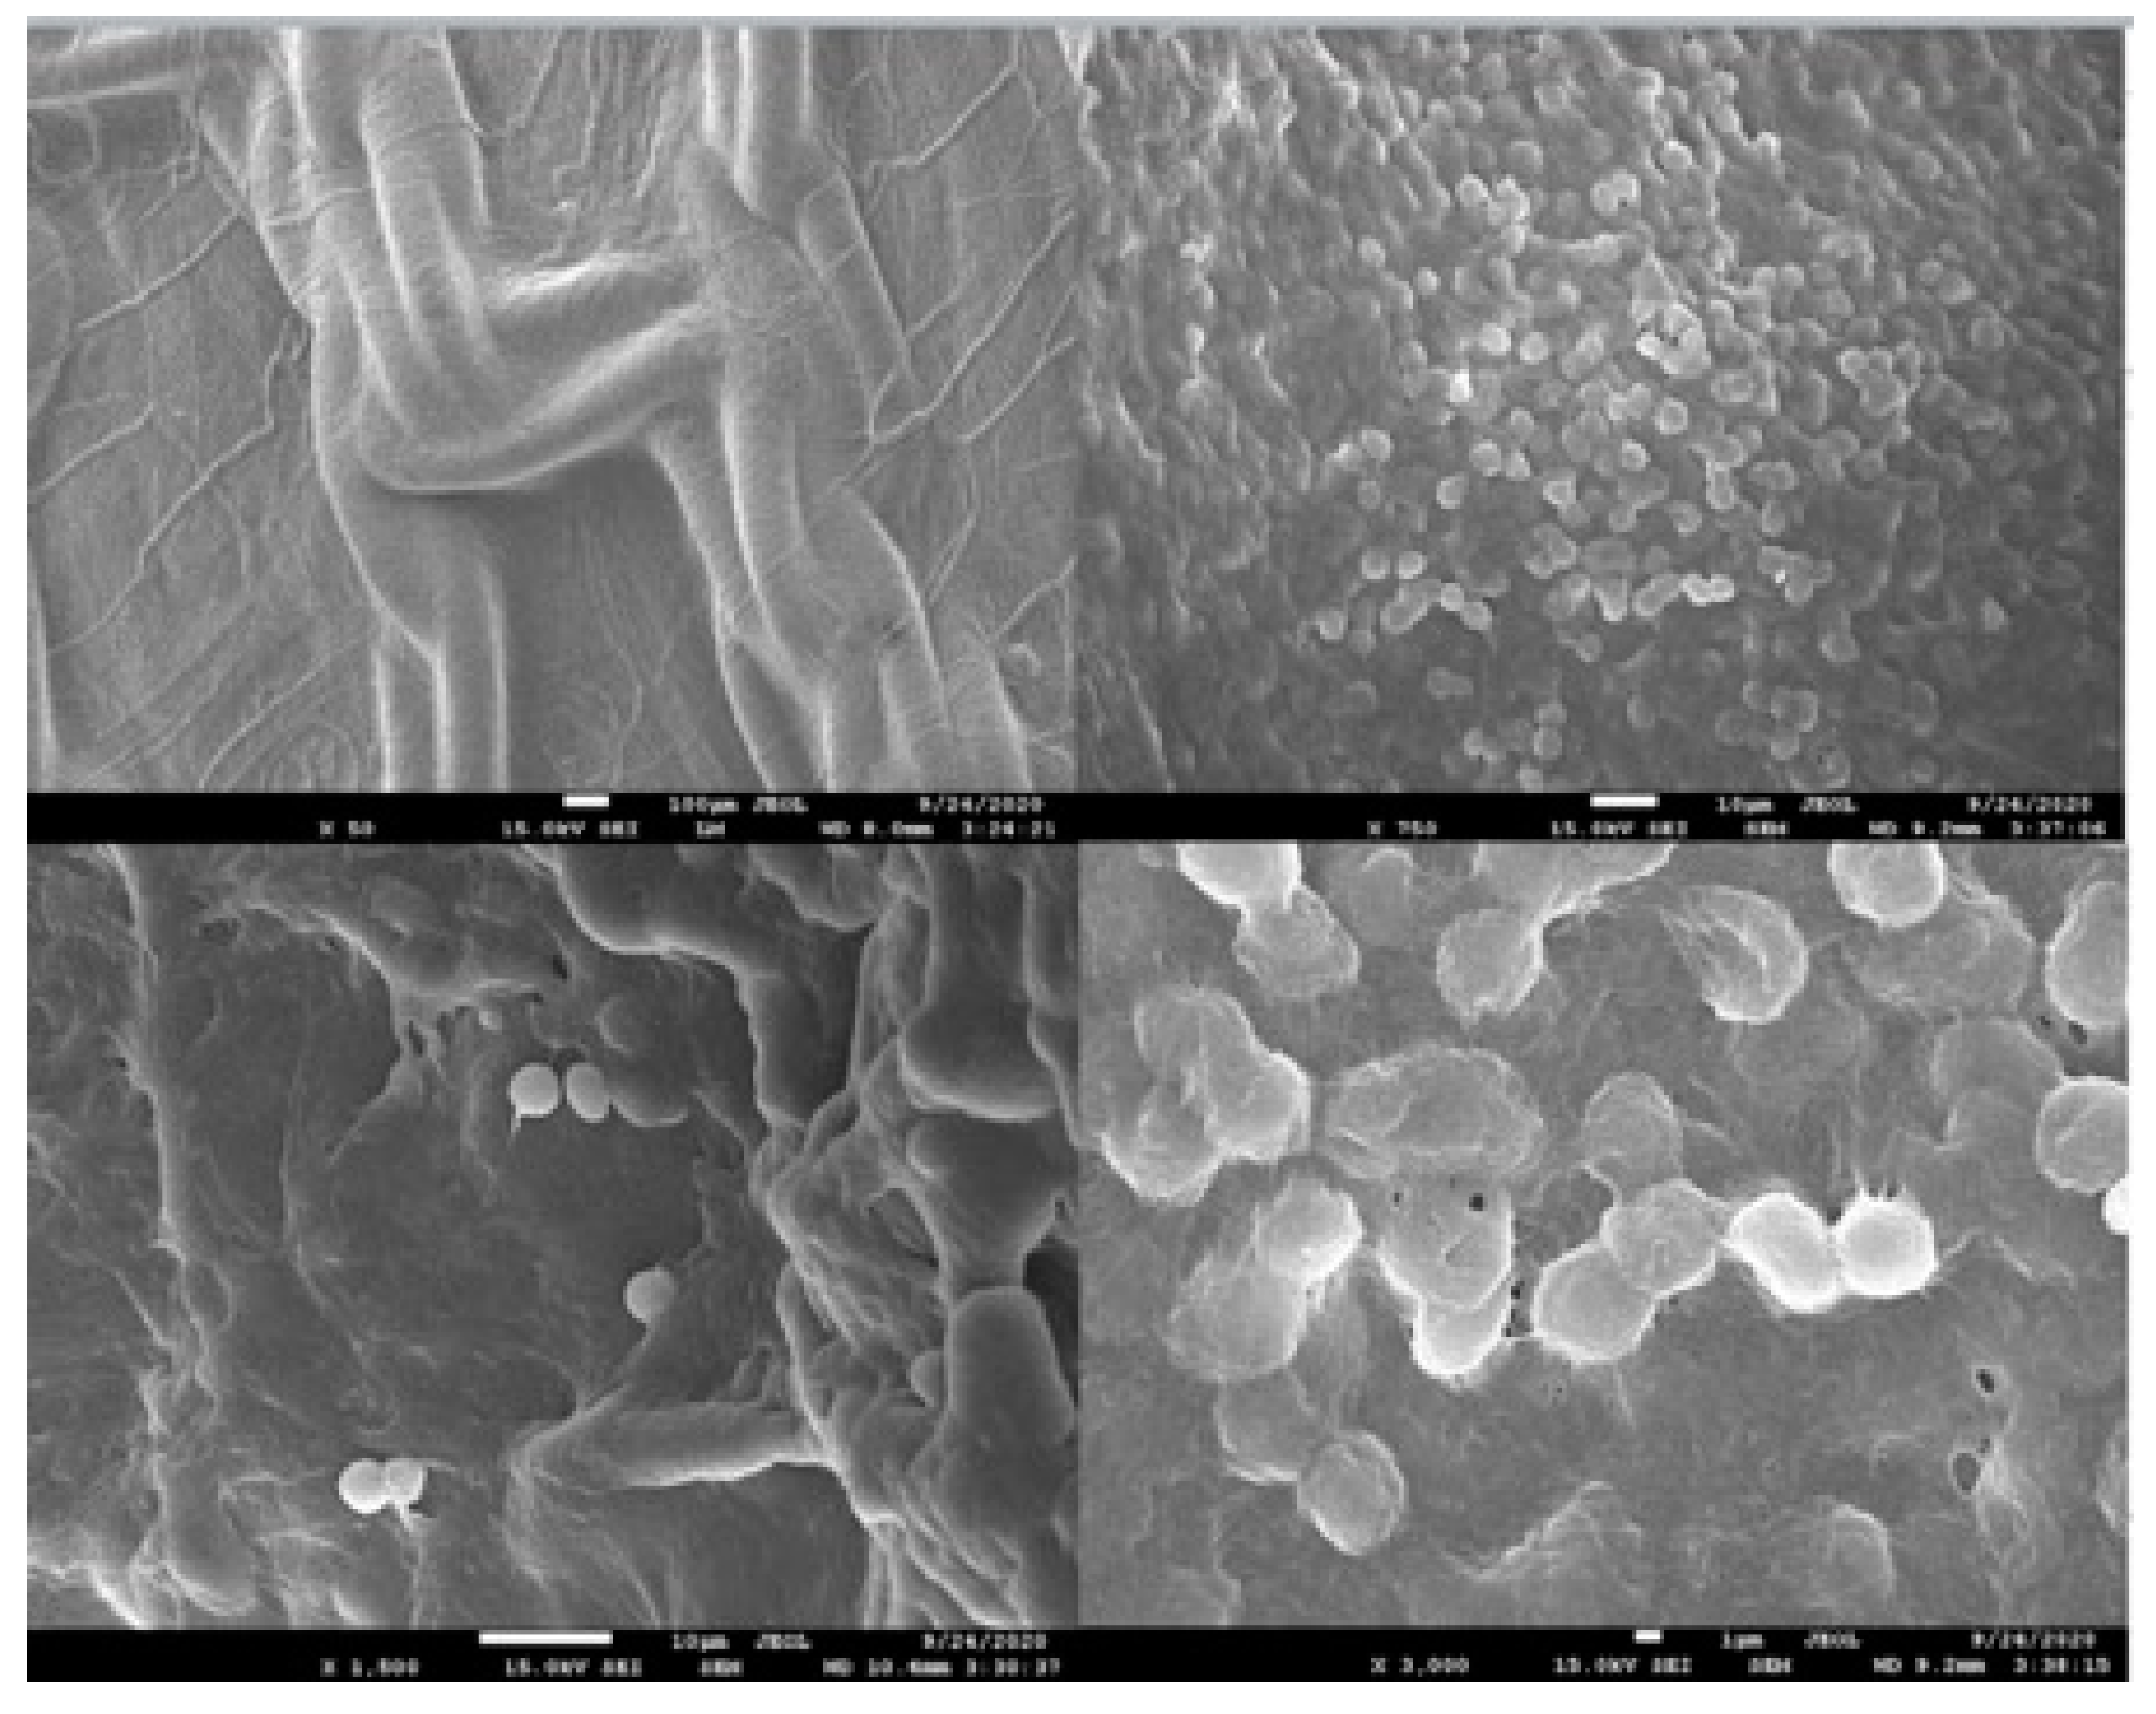

- Costello, C.R.; Bachman, S.L.; Ramshaw, B.J.; Grant, S.A. Materials Characterization of Explanted Polypropylene Hernia Meshes. J. Biomed. Mater. Res. Part B Appl. Biomater. 2007, 83B, 44–49. [Google Scholar] [CrossRef] [PubMed]